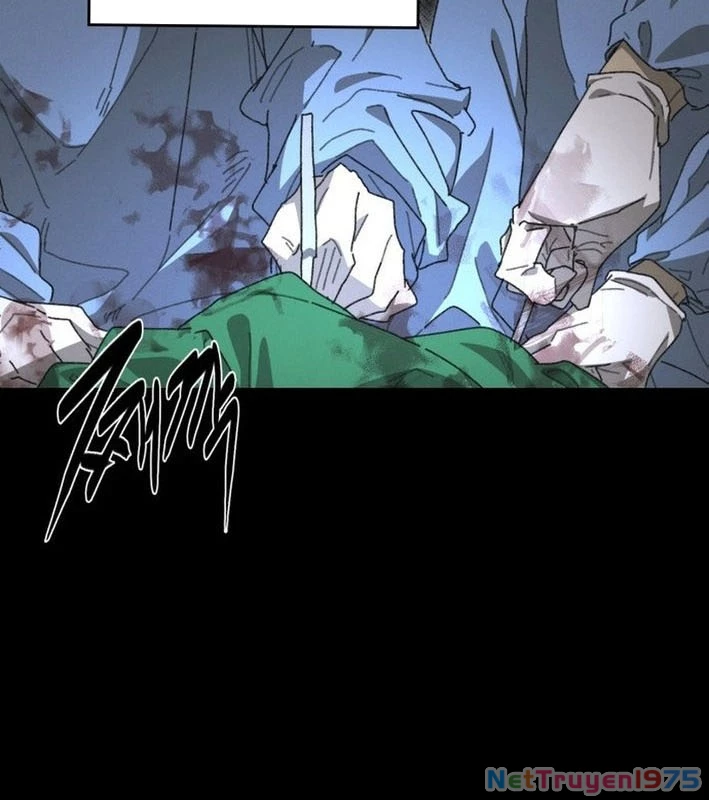

Kẻ Chôn Cất Quái Vật - Chapter 1